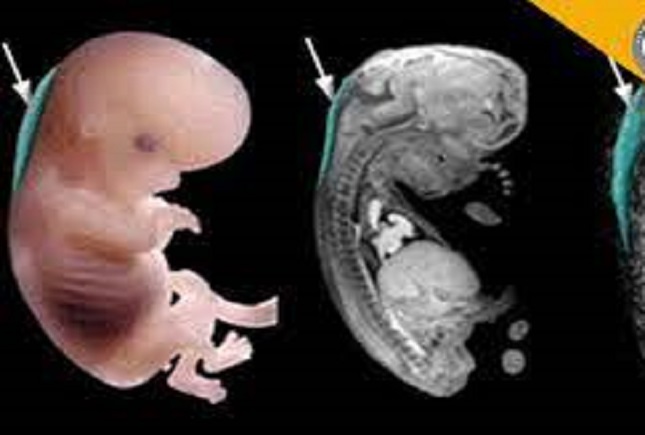

جامعه ۲۴ - به گفته محققان مرکز علوم بهداشت دانشگاه تگزاس در هیوستون آمریکا این دارو با عنوان ۱۷ آلفا هیدروکسی پروژسترون کاپروات (۱۷-OHPC) یک پروژسترون مصنوعی است که اغلب در دهههای ۱۹۵۰ و ۱۹۶۰ توسط زنان استفاده میشد و امروز نیز برای کمک به جلوگیری از زایمان زودرس برای زنان تجویز میشود. پروژسترون به رشد رحم در دوران بارداری کمک و از انقباضات اولیه که ممکن است منجر به سقط جنین شود، جلوگیری میکند.

مورفی گفت: یافتهها نشان میدهد مصرف این دارو در دوران بارداری میتواند رشد اولیه را مختل کند و ممکن است خطر ابتلا به سرطان را در چندین دهه بعد افزایش دهد. با استفاده از این دارو اثرات یک هورمون مصنوعی مشاهده میشود.